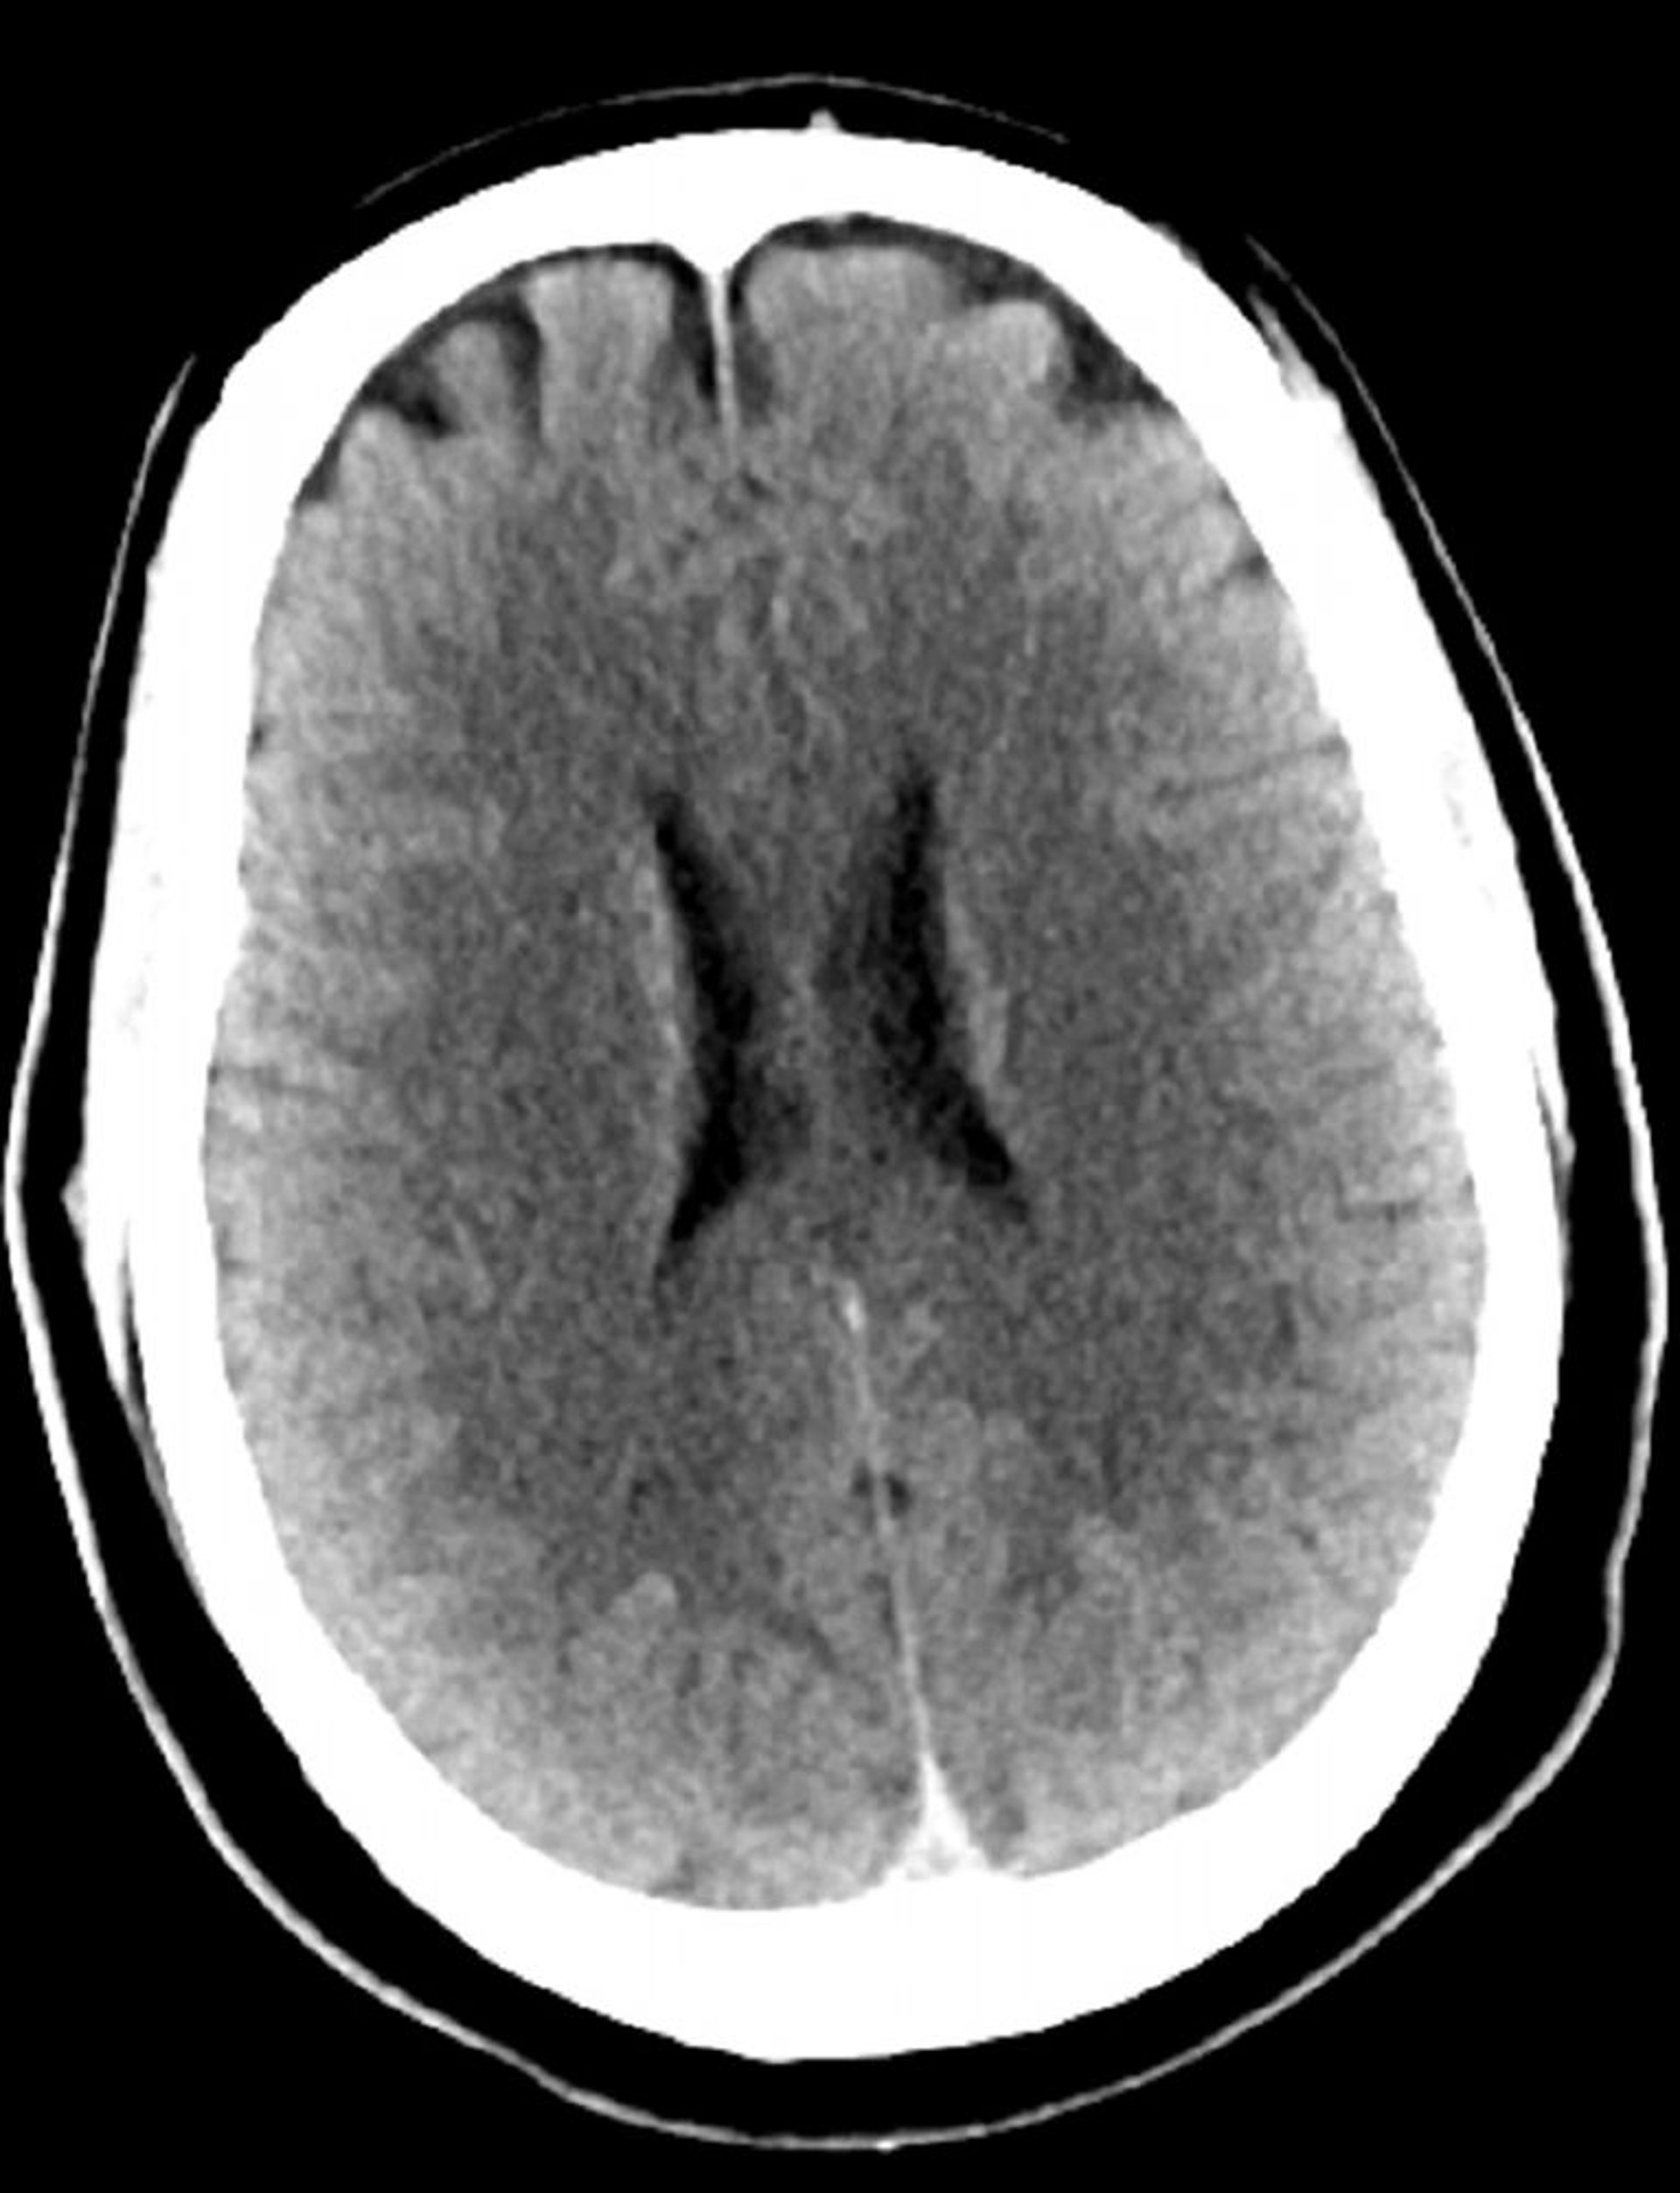

Tomodensitométrie normale de la tête (adulte 30 ans) – Diapositive 3

Cette image est une TDM normale de la tête d'un jeune adulte âgé de 30 ans. Il n'y a pas de liquide intra- ou extra-axial ou d'hémorragie. La différenciation gris-blanc est préservée. La taille du ventricule et la forme des sillons semblent normales.